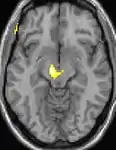

La morphométrie voxel par voxel (VBM) montre les différences structurelles des zones du cerveau

Les images par tomographie à émission de positron indiquent les régions du cerveau qui sont activées lors de la douleur, par rapport aux périodes sans douleur. Elles montrent les régions du cerveau qui sont toujours actives durant la douleur en jaune/orange (appelé "matrice-douleur"). La zone au centre (dans les trois vues) est spécifiquement activée uniquement pendant la crise. Les photos sur la ligne du bas (effectuées par VBM) montrent les différences structurelles entre les patients souffrant d'AVF et des personnes saines : seulement une partie de l'hypothalamus est différente[50],[51].

Il semble exister des anomalies microstructurales hypothalamiques bilatérales (en l'occurrence l'existence d'une hypertrophie)[52] sans que l'on sache si ces anomalies sont la cause ou la conséquence de la répétition des crises.